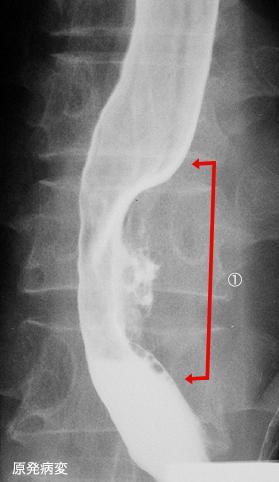

clasificación del pacienteTumor Epitelial Maligno/Carcinoma a Células Escamosas

parte(separada por órganos)esófago/inferior

método de exámenRayos X

clasificación ectoscópica de tumoresTipo 3(Tipo ulcerado de bordes infiltrados)/

diámetro mayor del tumor35 - 40

grado de penetracións(a)